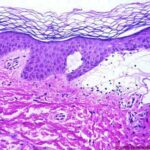

Histopathology. The bullous pemphigoid-like presentation described above is the most common form of EBA. The subepidermal blisters are inflammatory. The predominant infiltrating cells are lymphocytes and neutrophils in perivascular and focal interstitial array. Eosinophils are present in variable numbers . In the classic form, the subepidermal blisters are noninflammatory ; fibrosis and milia formation are often present. |

IF Testing. Examination of perilesional skin using DIF reveals linear deposition of complement at the basement membrane zone in the vast majority of cases. IgG is by far the most common immunoglobulin found, but IgM and IgA may be present as well. Increasing numbers of immunoglobulin subclasses noted at the dermal-epidermal junction favor a diagnosis of EBA over bullous pemphigoid. The presence of linear C3 at the dermal-epidermal junction alone favors bullous pemphigoid over EBA. However, use of routine DIF cannot reliably distinguish between bullous pemphigoid and EBA. IIF reveals circulating anti-basement membrane zone antibodies in up to 50%. |

The use of the salt-split skin technique leads to the appropriate diagnosis in most cases . The antibodies in EBA have specificity for the globular carboxyl terminus of type VII collagen and are deposited beneath the lamina densa. Therefore, on salt-split skin studies, IgG is on the floor and not on the roof of the split . |